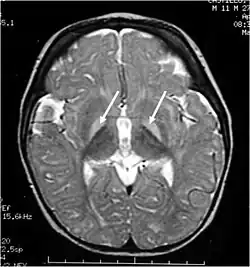

Brain MRI. Hyperintense basal ganglia lesions on T2-weighted images, showing Kernicterus bilirubin encephalopathy.

Kernicterus, is accumulation of high levels of unconjugated bilirubin within the basal ganglia of brain which can cause neurological lesions. Reduction of bilirubin in this state will not reverse the sequelae.[4] Christian Georg Schmorl coined the term Kernicterus in 1904.

These impairments are associated with lesions in the basal ganglia, auditory nuclei of the brain stem, and oculomotor nuclei of the brain stem. Cortex and white matter are subtly involved. Cerebellum may be involved. Severe cortical involvement is uncommon.